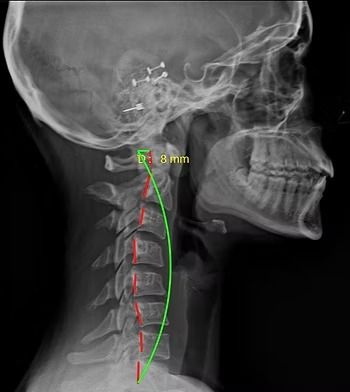

Starting off, we're going to be looking at the side of the neck. With every patient, the first thing we're looking at is the curvature. We're looking at this green curvature line and that's where we ideally want to see the bones of the spine aligned. When we're looking at the red line here next to the green one, that's actually the patient’s alignment right now. You can see that it's straightened out and we don't have as much of that natural curvature that we're looking for in the cervical spine. The second thing we analyze is the amount of space in between the bones or vertebrae. Near the top of the cervical spine, you can see how the spaces are thicker and then when you get down to the lower cervical vertebrae, they're thinner. What is happening here is the disc space is decreasing and that's important to notice because it is the first sign of degeneration in the spine.

Cervical X-Ray patient standing normally, looking straight ahead

With the next patient, you can see a bigger gap between the red and green line. His head is way more forward and the cervical or neck curve is much more straightened out. The significance with that is the more your head is forward, the more force and pressure it's going to not only put on your neck but the rest of your spine as well. Imagine a rubber band that is stretched and stretched and becomes more tight. The other part with posture too is that the further forward the head goes, it actually decreases your ability to breathe and limits a lot of other functions in the body.